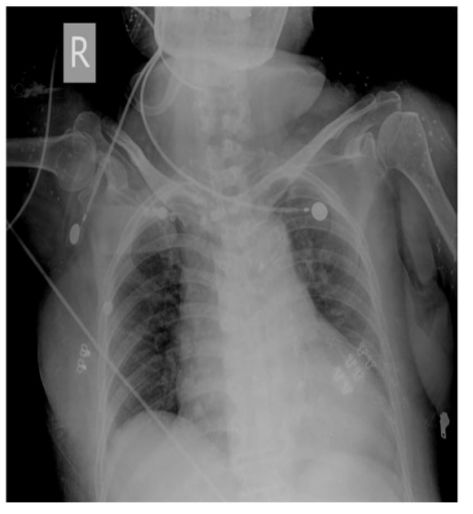

15. 50歲男性,患有糖尿病,胰臟癌及恐慌症,因突發性呼吸困難至急診求診。病患並無明顯胸痛或冒冷汗,意識清楚但情緒緊張,理學檢查發現體溫36.5℃,血壓 145/95 mmHg,脈博112/min節律規則, 呼吸 24/min快且深;四肢冰冷有輕微發紺現象。頸靜脈壓12 cm H2O,無明顯心雜音。呼吸音雙側正常,腹部平坦無壓痛,四肢活動正常亦無水腫。護理人員給予脈衝血氧定量計 (pulse oximeter) 偵測發現SpO2 84%,急診醫師隨即指示使用Venturi mask O2 35%。約半小時後,病人自覺症狀略為減緩,此時之動脈氣體分析: PH 7.50, PaO2 70mmHg, PaCO2 25 mmHg, HCO3 23 mEq/L, one touch blood glucose 320 mg/dl. EKG除竇性頻脈外其餘正常,胸部Ⅹ光如附圖,下列診斷何者最有可能? (A) Acute pulmonary embolism (B) Panic disorder related hyperventilation syndrome (C) Diabetic ketoacidosis (D) Endobronchial foreign body (E) Bronchial asthma